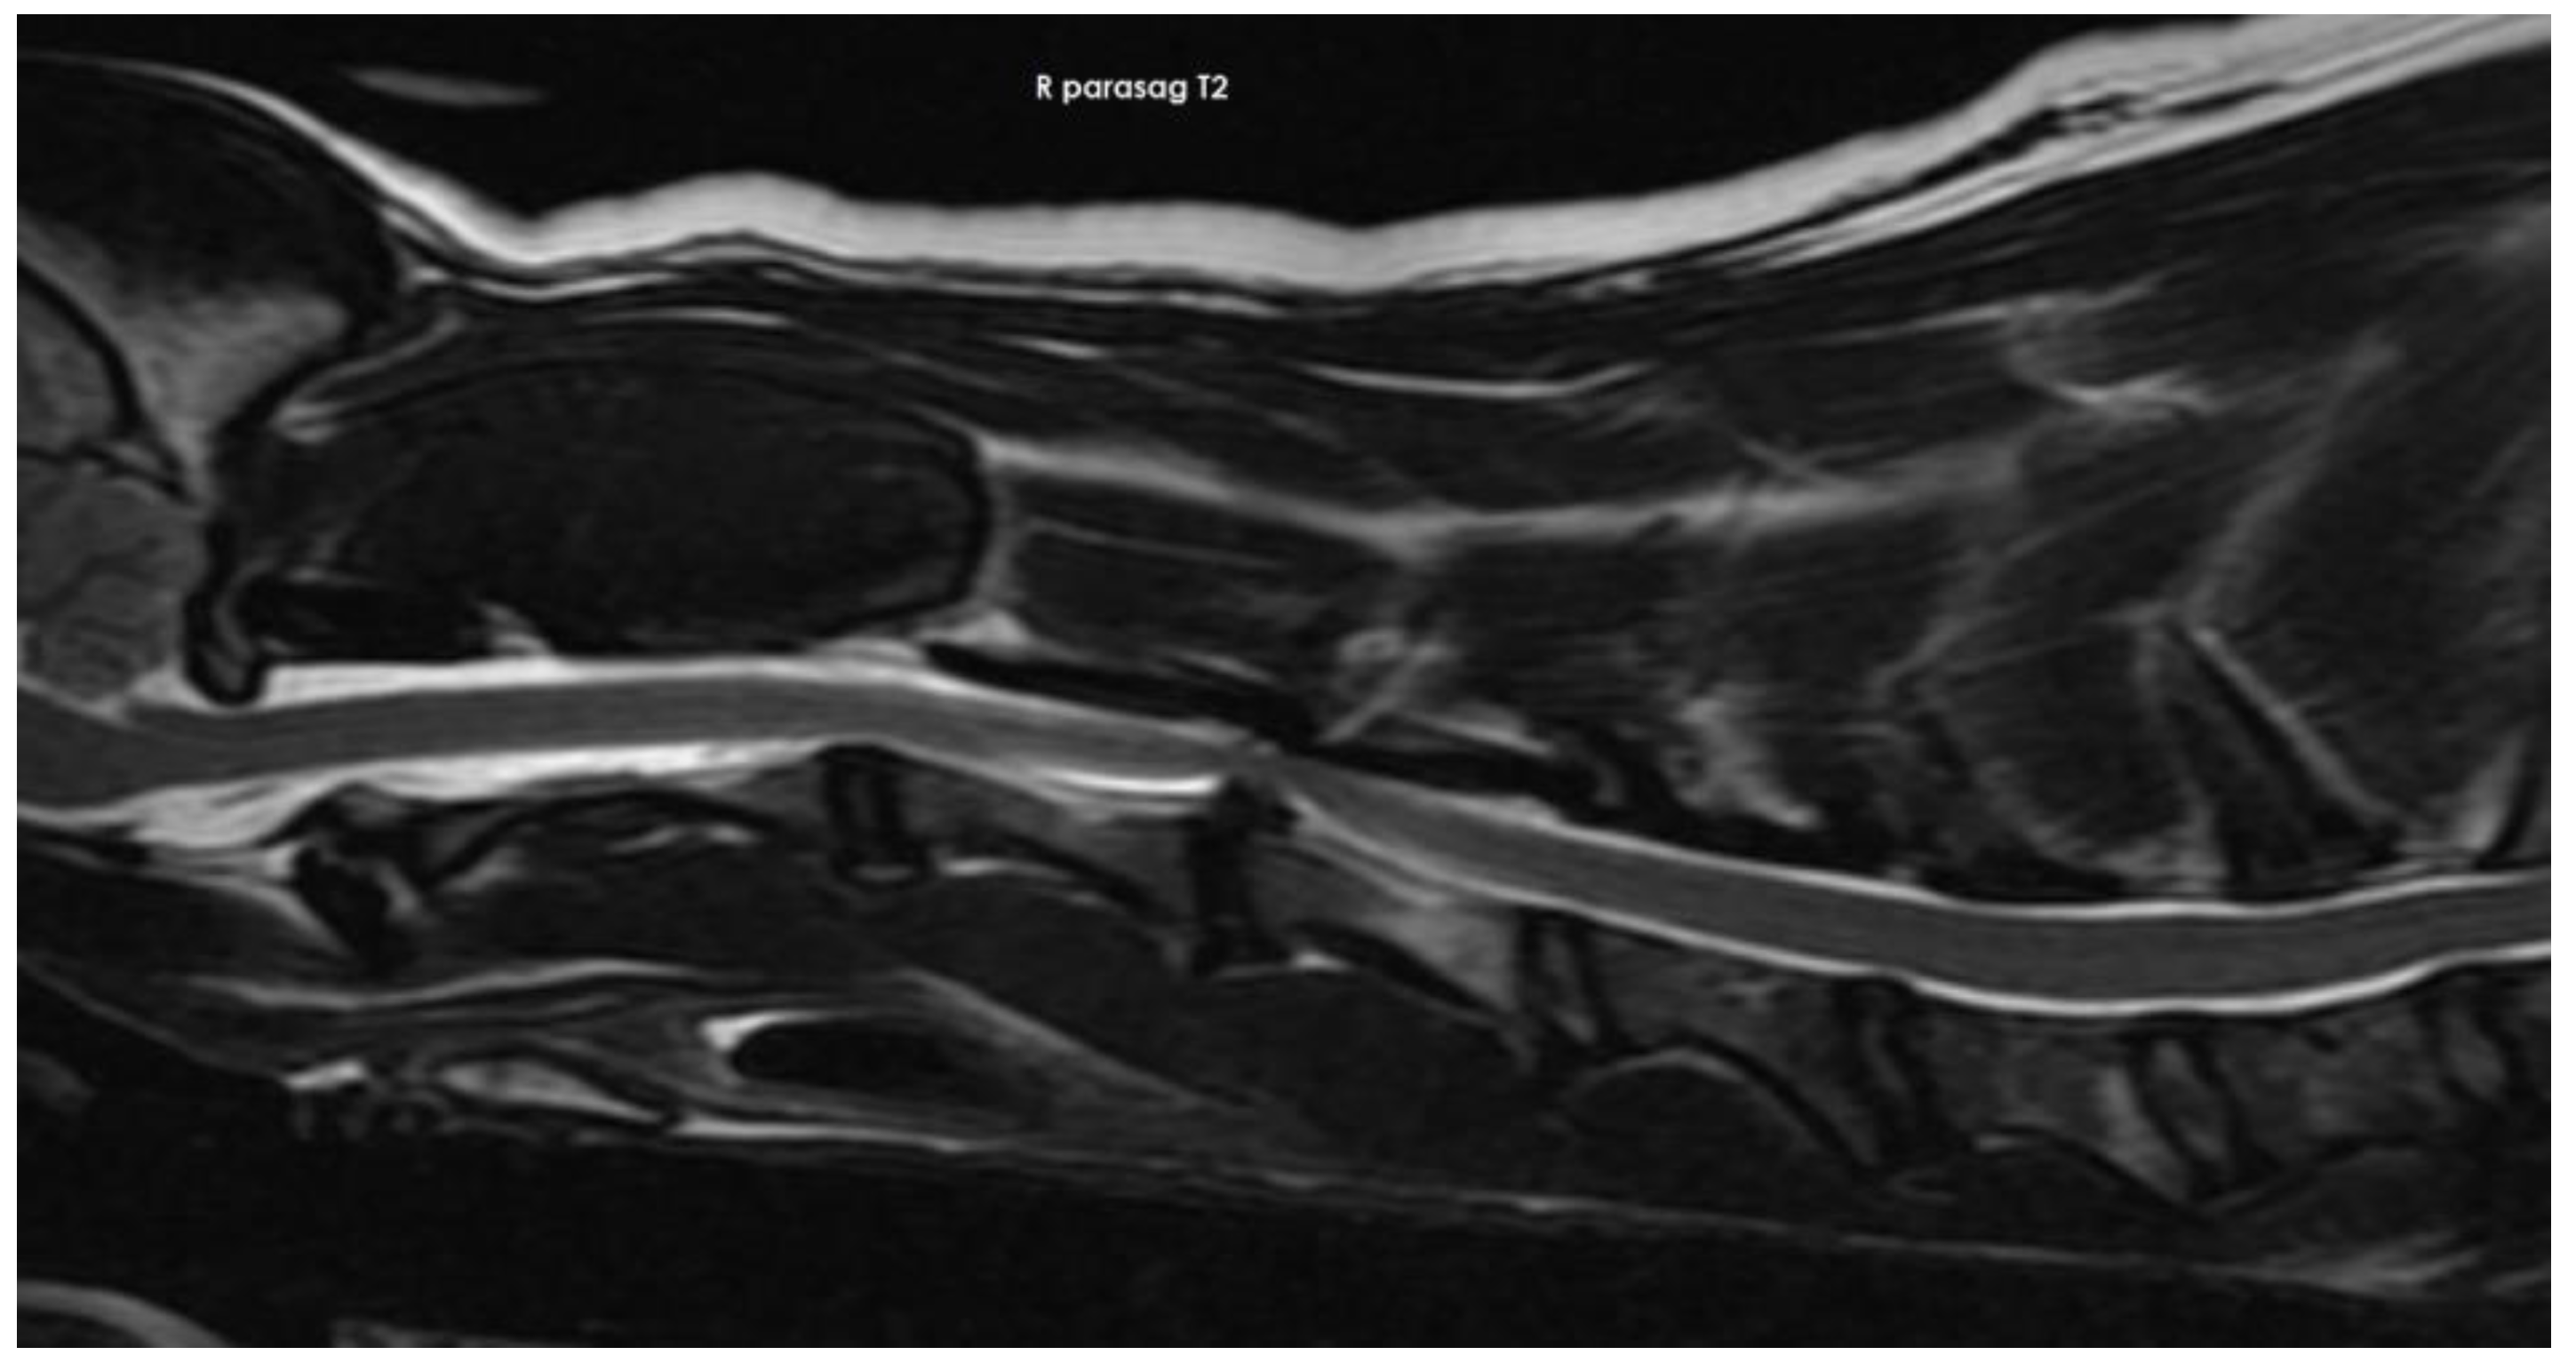

3.2. Diagnostic Imaging